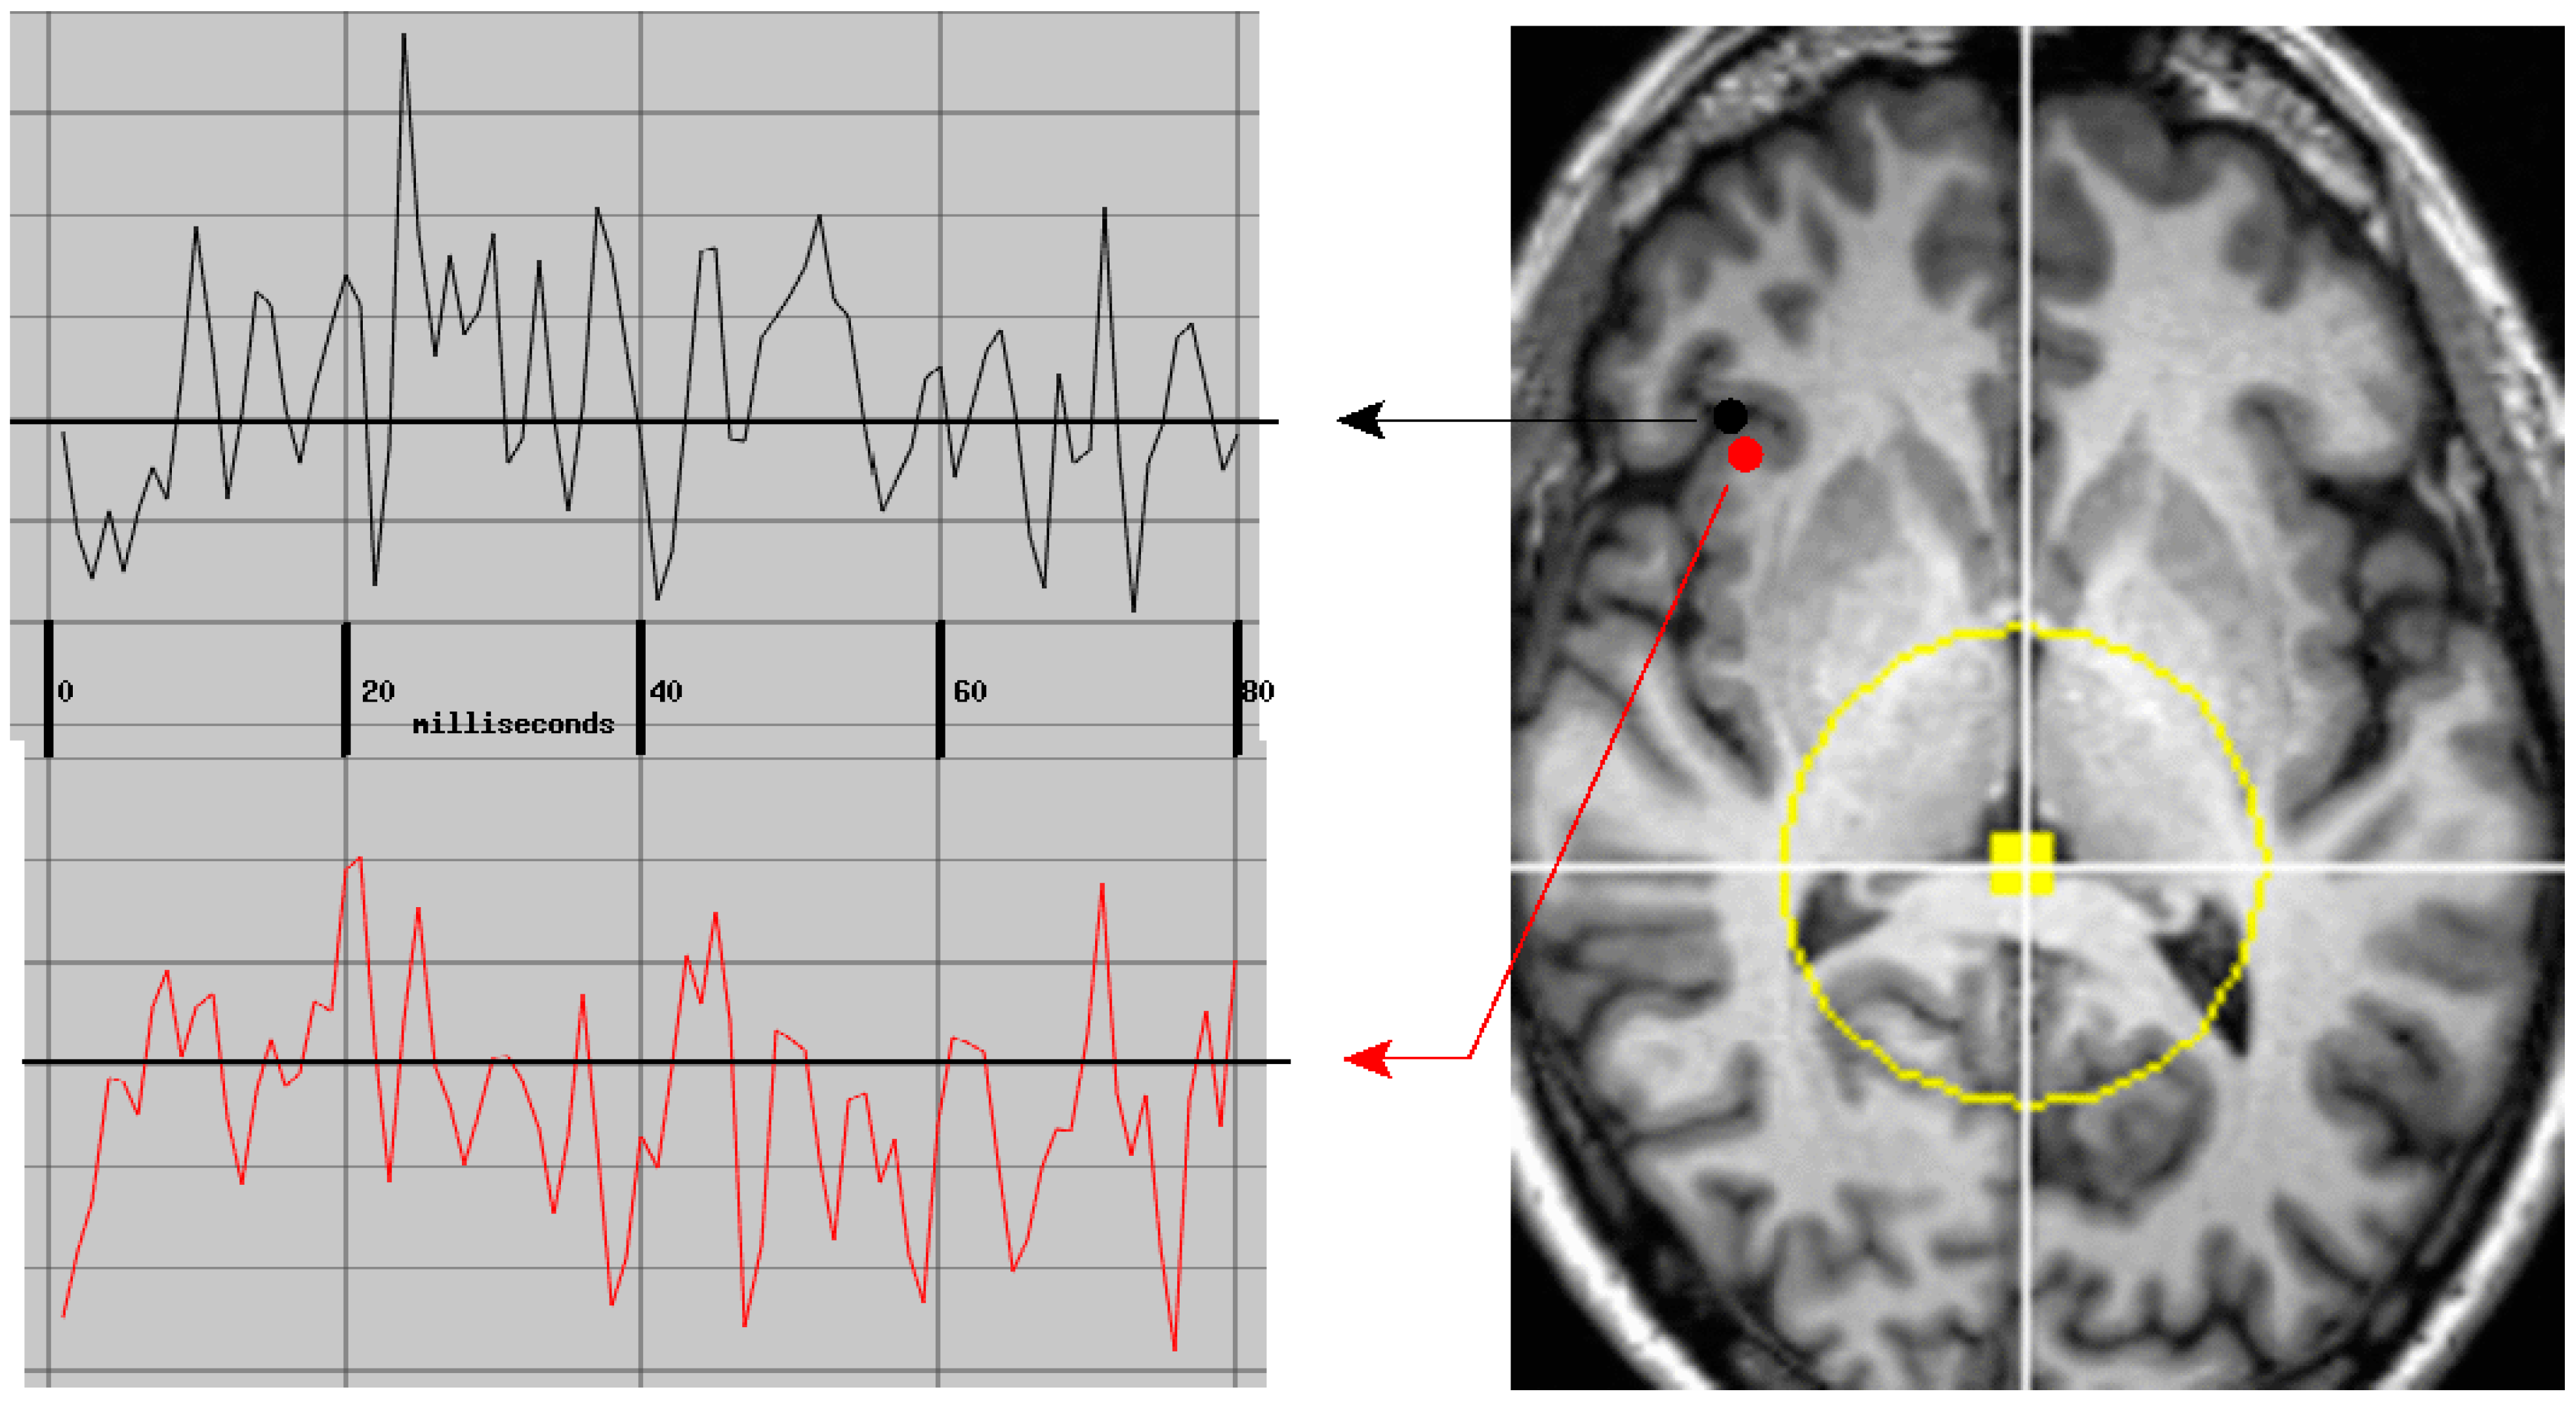

2.4. Differential Activity: Cortical vs. Adjacent White Matter Regions

6.3. Cortical vs. Adjacent White Matter Regions